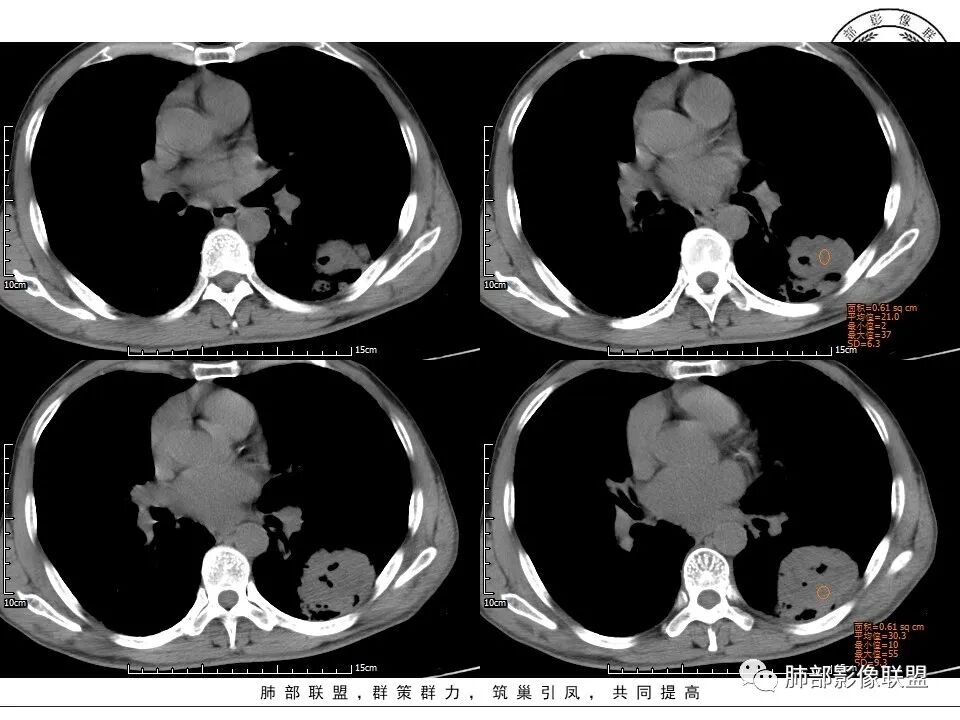

1、老年男性,肺气肿背景,咳嗽胸闷一个月,血象不高,C反应蛋白无明显升高,无发热。

2、左肺下叶近胸膜下较大肿块,土豆样外形,边缘清楚,膨隆分叶,未见明显渗出;病灶内部多坏死及空洞,似鬼脸征,坏死边界不清;增强扫描轻度不均匀环形强化;近端支气管似有阻塞截断。肺门纵隔未见肿大淋巴结。

3、综上所述,考虑恶性,鳞癌可能。

患者中老年男性,咳嗽、胸闷1月余。查肝肾功能、血糖、血脂、心肌酶异常不明显;血常规提示血象不高,轻度贫血;血沉、C反应蛋白、降钙素原无明显升高。胸部CT:肺气肿背景,左肺下叶胸膜下不规则肿块,边缘光滑,边界清楚,见浅分叶,其内见多发分隔空洞及坏死,似鬼脸征,支气管显示欠清,增强不均匀强化。右肺下叶胸膜下间质纤维化改变。综合肿块考虑恶性病变,鳞癌或肉瘤样癌可能大,鉴别隐球菌。